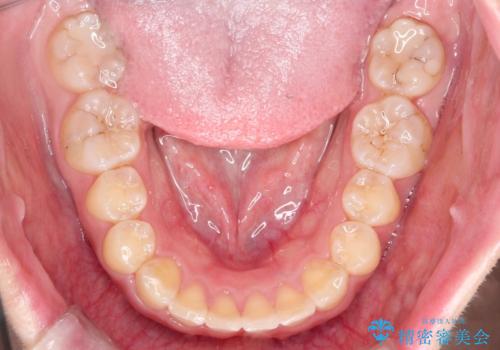

初診時の歯並びの状態としては、上の前歯が下に対して前に飛び出た上顎前突という状態で、前歯は大きく前に飛び出した状態により患者様も口の閉じづらさを感じているとのことでした。また上顎に軽度の叢生(ガタガタ)がありました。

抜歯は行わず上顎の奥のスペースを利用して歯をスライドする方法の他に歯列弓の拡大やディスキング(歯と歯の間の隙間を作る処置)を行い叢生を改善しました。